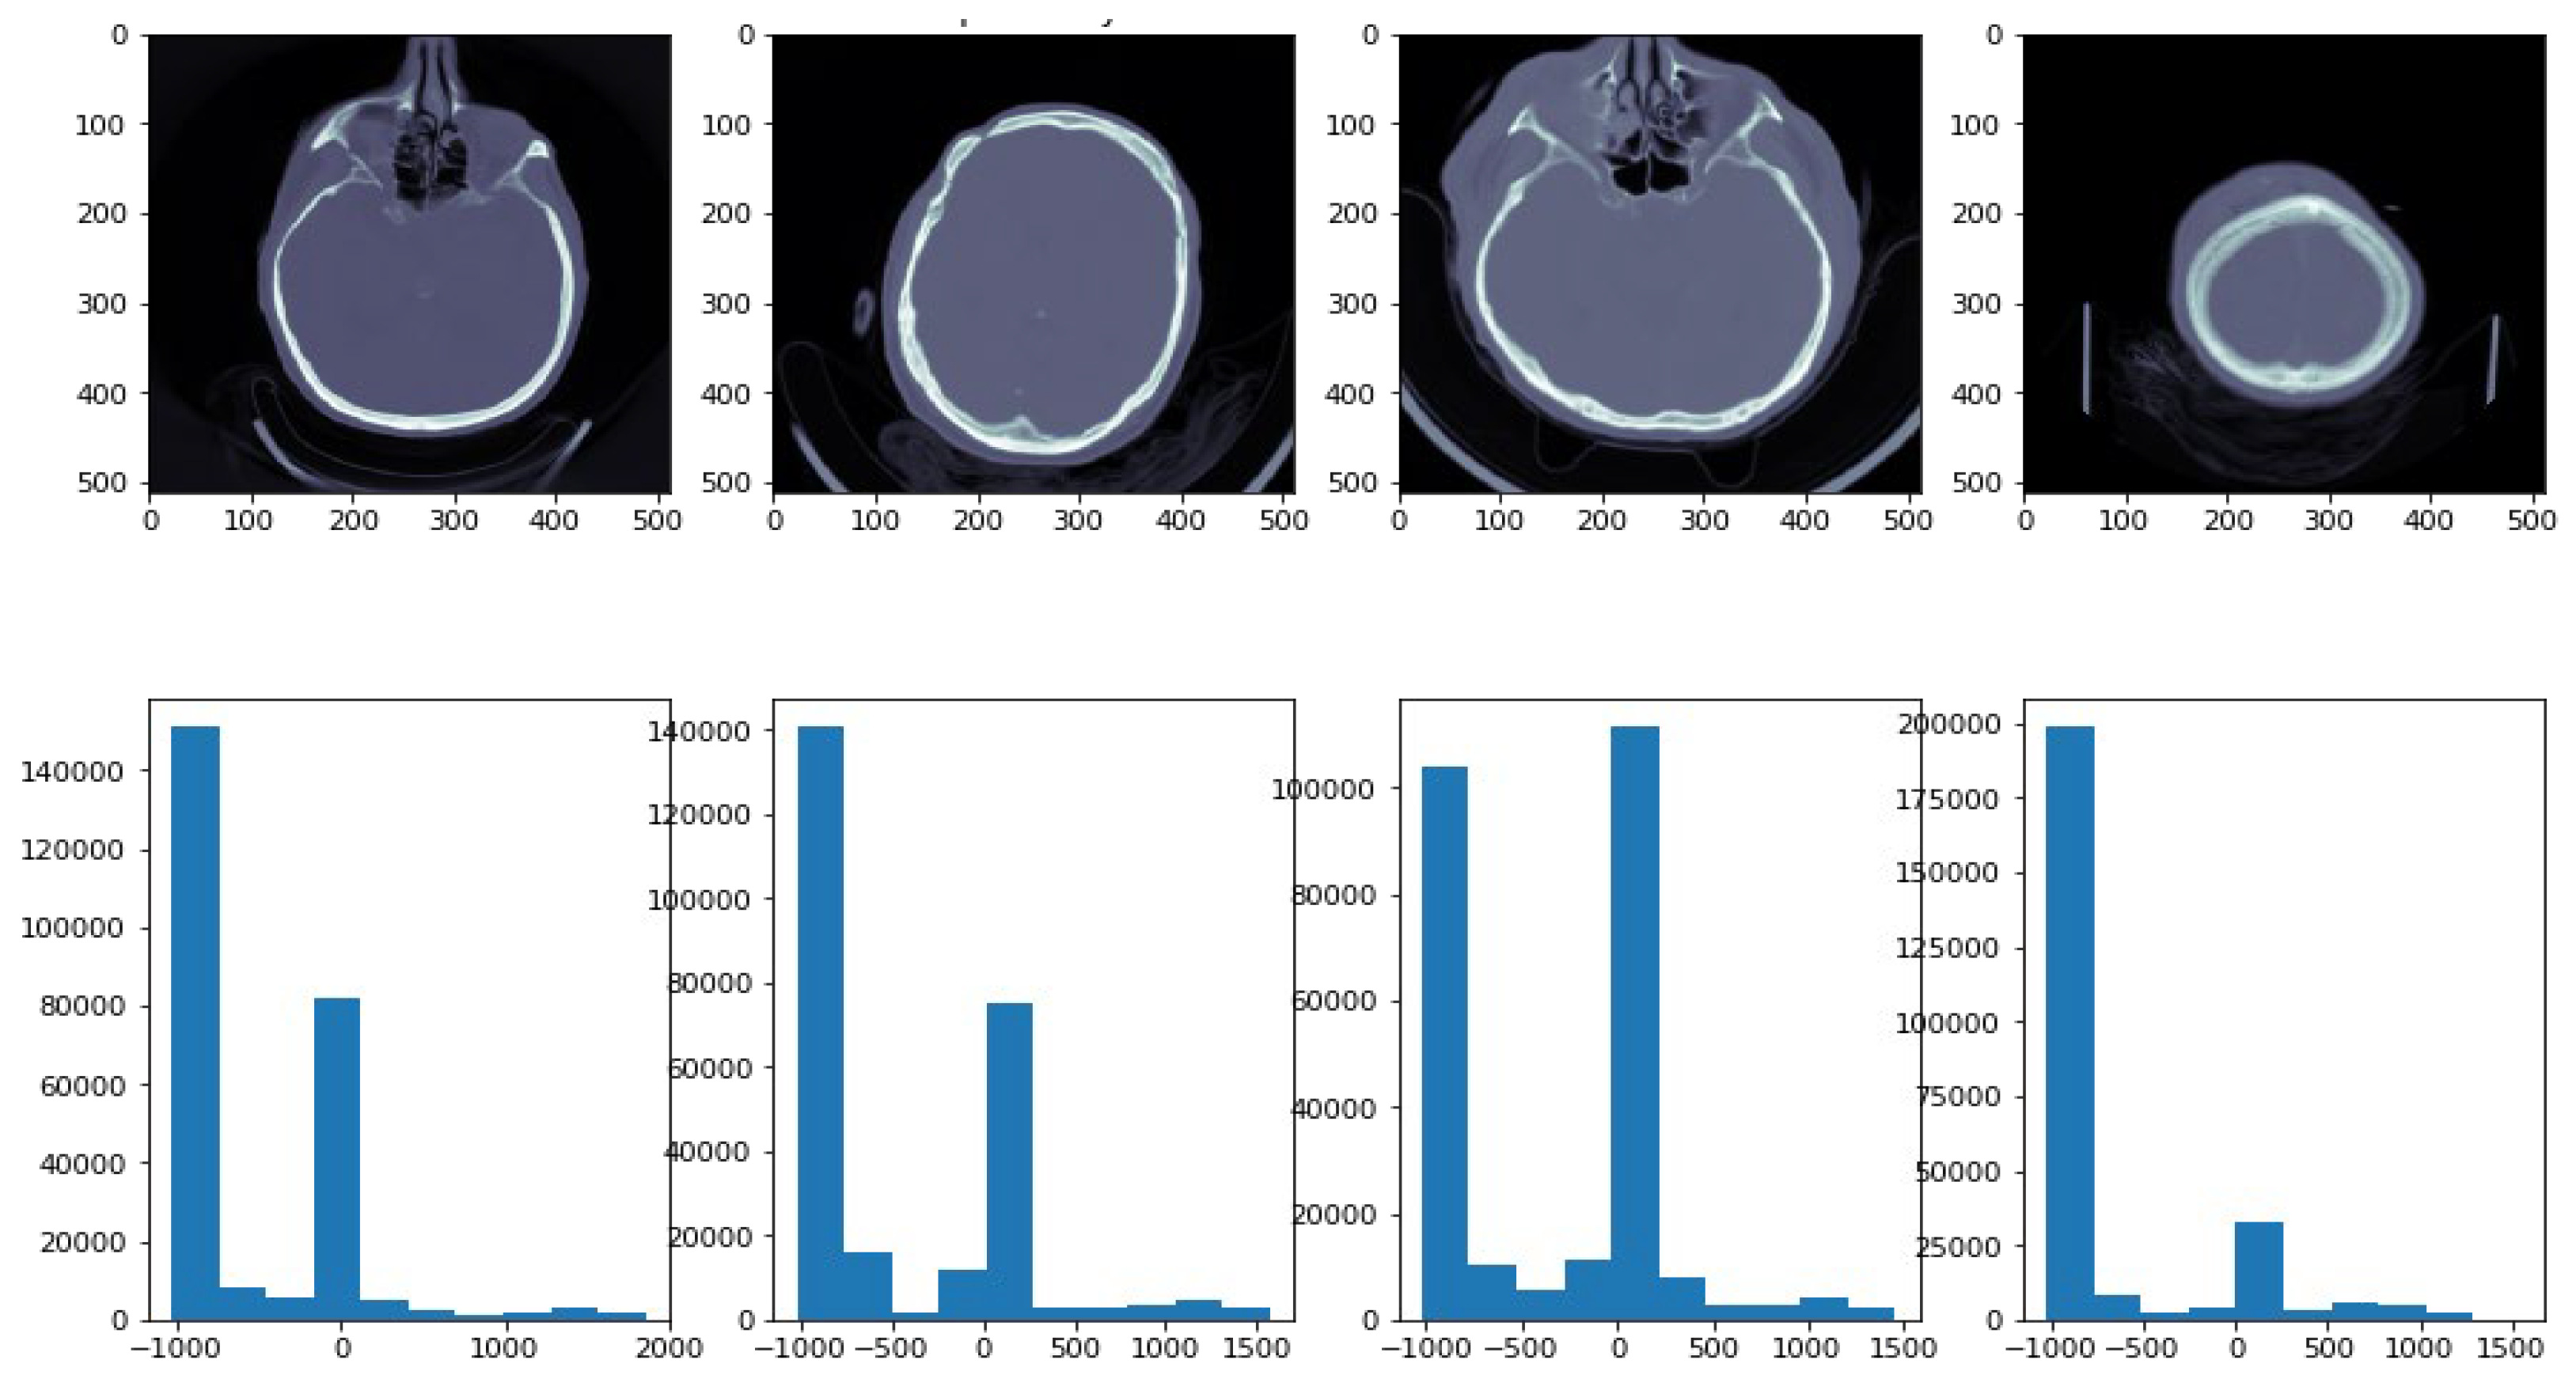

3.3. Hounsfield Scale

Grayscale in medical CT imaging is measured in Hounsfield Units (HUs). There are 4096 values (12 bits), and the scale ranges from −1024 HU to 3071 HU (zero is also a value). Using this scale, it is possible to correlate the attenuation of CTs with the density of tissues [28]. Using the “windowing” technique, CT images are enhanced based on their contrast. If two parameters are specified, the window level and the window width, it is possible to see the given window (mapped into the entire grayscale range (0 to 255)). A white color would be perceived if the value was greater than (l + w/2), whereas a black color would be perceived if the value was lower than (l − w/2). There are two important window settings for CT images: Bone window and Brain window. We used Python’s DICOM library, using command line APIs including Rescale Intercept and Rescale Slope. The rescaling of CT images to Hounsfield units was carried out in different steps using Python API, as shown in Figure 2. This method was used to determine the values of the histograms of the images. Figure 2 shows ICH images with their corresponding histograms.

Figure 2.

ICH images with their corresponding histograms. In the histogram, the x-axis demonstrates image intensity, while the y-axis demonstrates pixel count.